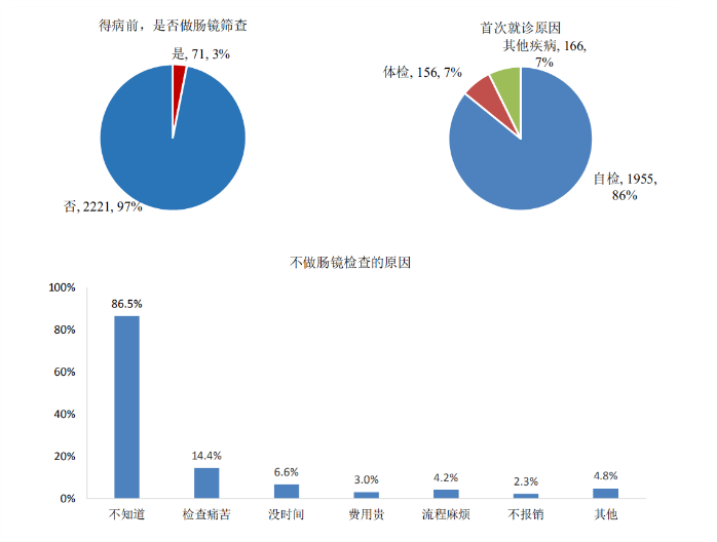

2020年9月,发表在《美国胃肠病学杂志》(American Journal of Gastroenterology)的一项研究通过分析新罕布什尔州结肠镜注册数据发现,40岁起增加患结直肠晚期肿瘤(AN)的风险。同月,我国发布首个大规模结直肠癌患者诊疗现状调查中期结果,据调查报告:

97%的结直肠癌患者患病前未做过肠镜检查,其中86.5%的患者未做肠镜检查由于对结直肠癌早期筛查缺乏认知,不知道需要定期做肠镜筛查。85.8%的结直肠癌患者是因为发现便血、严重腹泻或者腹痛等疑似症状再去做肠镜检查。这些数据触目惊心,难怪我国的直肠癌一经发现已有83%的患者处于中晚期。